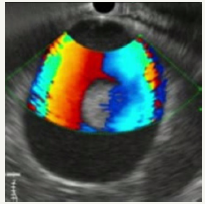

Figure 12A:EUS picture of aneurysm.

Figure 12B:Communication with splenic artery.

Figure 12C:Dopler color view.

Figure 12: Clinical case of aneurysm of splenic artery that was regarded as a pseudocyst on CT without contrast. Contrast wasn`t use because patient had chronic renal failure.